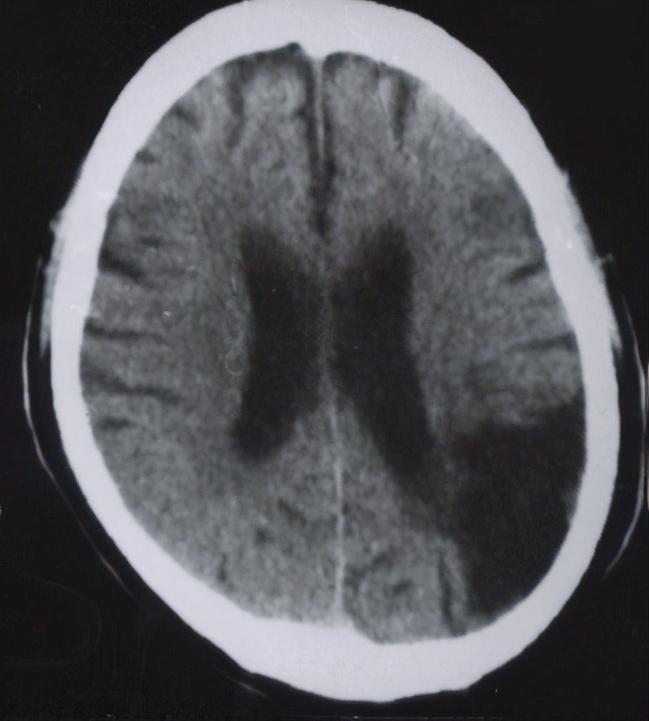

头颅CT显示左侧顶颞叶陈旧性脑梗塞